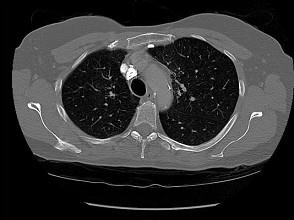

问题 71岁,女,发现颈部淋巴结肿大,胸片和CT检查如图,请选出最可能的诊断 ( )

选项 A、肺癌 B、神经源性肿瘤 C、淋巴瘤 D、淋巴结核 E、结节病

答案 C